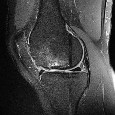

A 45-year-old female presents with sudden onset medial knee pain while squatting. MRI shows a medial meniscus posterior root tear. Biomechanically, what is the consequence of this specific injury on the knee joint?

Options:

Correct Answer: Kinematics equivalent to a total medial meniscectomy

Explanation:

A complete posterior root tear of the medial meniscus leads to a complete loss of hoop stresses, resulting in radial extrusion of the meniscus during axial loading. Biomechanically, this is equivalent to a total medial meniscectomy, significantly decreasing the contact area and markedly increasing peak contact pressures, leading to accelerated osteoarthritis.